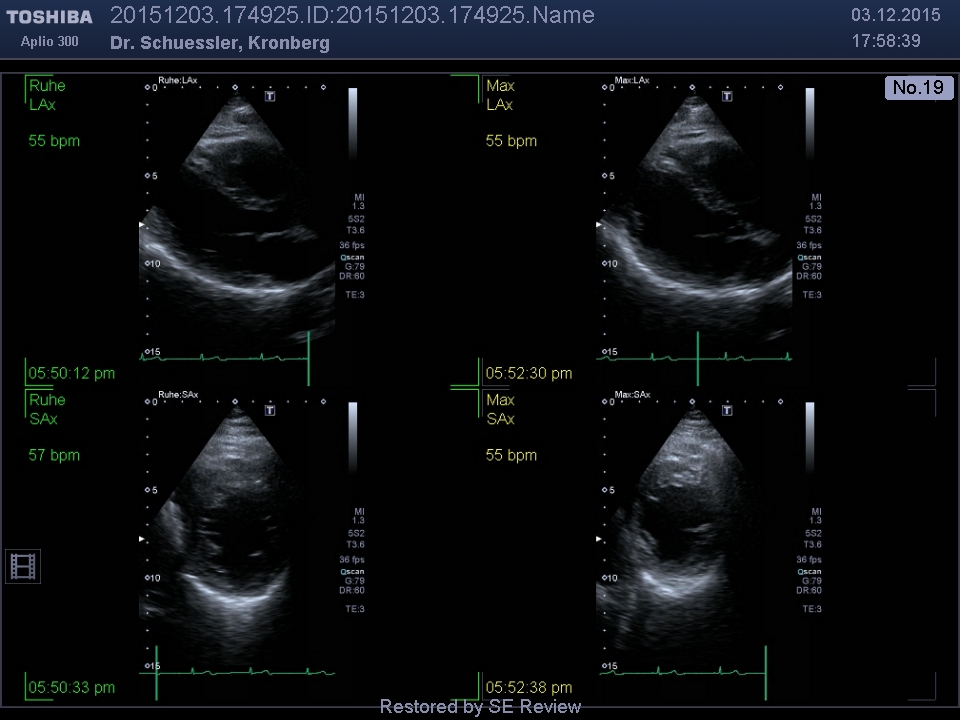

Die Streßechokardiographie wird vorwiegend bei Verdacht auf - oder zum Ausschluss einer koronaren Herzerkrankung eingesetzt. Sie erlaubt einen direkten Vergleich der Bewegung des Herzens in Ruhe und unter körperlicher Belastung. Hierzu werden zunächst in Ruhe, mittels Echokardiographie, Aufnahmen der Herzbewegung erstellt. Gleiches erfolgt nach Erreichen der maximalen Last auf dem Ergometer. Sofern es unter Belastung zu einer Minderdurchblutung des Herzmuskels kommt, lässt sich dies in der vergleichenden Betrachtung der Aufzeichnungen durch das Auftreten einer Bewegungsstörung des Herzmuskels erkennen.

Die Auswertung der Untersuchung erfolgt mittels computergestützter Analyse der Bewegung und Funktion der einzelnen Segmente des Herzmuskels